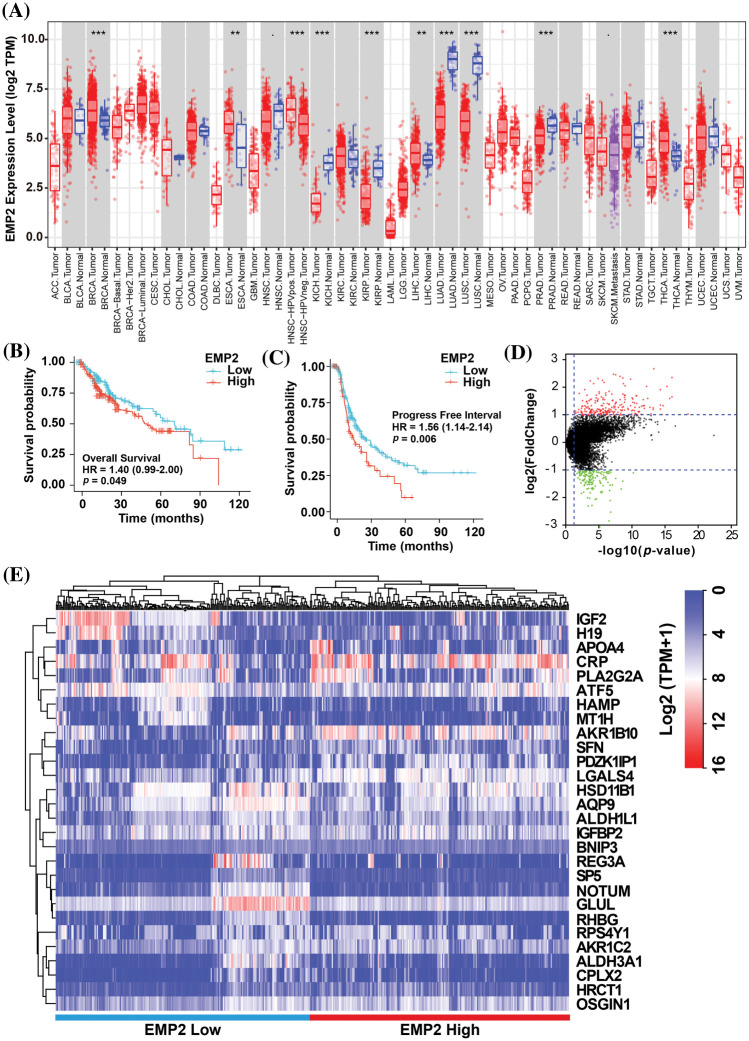

To investigate EMP2 transcript levels in 36 common human tumors, we analyzed data from the TCGA-TIMER https://cistrome.shinyapps.io/timer/ and Oncomine databases https://www.oncomine.org/resource/login.html. Analysis of the TCGA RNA-seq data revealed significant differences in EMP2 expression levels across various tumor tissues. Among the 18 tumor types with paired normal and tumor samples, EMP2 mRNA expression was significantly higher in BRCA, THCA, ESCA and HCC compared to their respective normal tissues. These results suggest that EMP2 is differentially expressed across multiple tumor tissues. However, the expression pattern is not consistent across all tumor types, with high expression observed in some tumor tissues and low expression in others. This suggests that EMP2 may have distinct roles in the initiation and progression of different cancer types, potentially contributing to the understanding of various malignancies (Fig. 2A). To evaluate the impact of EMP2 expression on overall survival, we performed Kaplan-Meier survival analysis on HCC samples, using the median value of EMP2 mRNA expression in HCC tissues as the cutoff. The results showed that HCC patients with high EMP2 expression had a median survival time of 49.7 months. Conversely, the low-expression group had a median survival time of 70.5 months, with roughly one-quarter of the patients surviving at the 100-month mark (p = 0.049, Fig. 2B). Additionally, we performed a comparative analysis of progression-free survival (PFS) in HCC patients (Fig. 2C). The results suggested that EMP2 mRNA expression levels exhibited a significant negative correlation with PFS in HCC patients (p = 0.006).

EMP2 is an autophagy-related gene in HCC

To identify significantly differentially expressed mRNAs, we performed a differential expression analysis of 374 HCC samples with high or low EMP2 expression. The analysis resulted in the identification of a list of significantly differentially expressed mRNAs. The volcano plot of the differentially expressed genes was generated to visualize the distribution of gene expression profiles (Fig. 2D). Each point on the plot represents a gene, with the color indicating whether the gene is differentially expressed. Furthermore, cluster analysis was performed on the characteristic differentially expressed genes found in the red and green regions, identifying 28 distinct autophagy-related genes. The cluster analysis results are presented in Fig. 2E. Interestingly, some of these genes, including IGFBP2 and BNIP3, are associated with autophagy [ref. 34–ref. 37]. This finding suggests a potential link between EMP2 and autophagy processes. The WGCNA method was employed to analyze the differentially expressed genes in HCC tissues categorized by high and low expression of EMP2. The hierarchical clustering was initially performed using the hclust function to eliminate outlier sample data. An appropriate soft threshold (b) was calculated as the weighting coefficient for the adjacency function through computation. Subsequently, the WGCNA package was used to compute the correlation matrix and adjacency matrix for EMP2 gene expression profiles, as illustrated in Fig. 3A. Univariate analysis identified two modules, the turquoise module and the yellow module, which exhibited significant associations with high EMP2 expression in HCC tissues (Fig. 3B). GO annotation analysis was further conducted on the 437 genes enriched in the turquoise and yellow modules, revealing key functions such as peptidase regulator activity, collagen-containing extracellular matrix, macroautophagy, small molecule catabolic process, and others (Fig. 3C). Moreover, enrichment patterns of differentially expressed genes were observed in various KEGG pathways, such as complement and coagulation cascades, chemical carcinogenesis, autophagy-animal, carbon metabolism, cholesterol metabolism, and others (Fig. 3D). GSEA pathway enrichment analysis was further performed on these differentially expressed genes. The analysis revealed that these genes were primarily enriched in two GO terms, cell cycle and ECM-receptor interaction (Fig. 3E), and three KEGG pathways, autophagy, chemical carcinogenesis, and longevity regulating pathway (Fig. 3F).